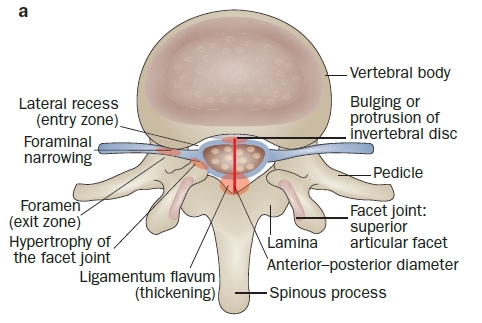

Lumbal spinal stenos (LSS) innebär en anatomisk förträngning av ryggradskanalen med påföljande nervkompression och är ofta förknippad med symtom på neurogen claudicatio. En normal anterior-to-posterior (AP) diameter på ryggradskanalen ligger någonstans mellan 22-25 mm. I relativ LSS har denna diameter minskat till 10-12 mm. Detta är ofta en symptomfri sjukdom. Absolut LSS visar en ryggmärgskanal med en AP-diameter på mindre än 10 mm och är ofta symtomatisk.

Lumbal spinal stenos (LSS) innebär en anatomisk förträngning av ryggradskanalen med påföljande nervkompression och är ofta förknippad med symtom på neurogen claudicatio. En normal anterior-to-posterior (AP) diameter på ryggradskanalen ligger någonstans mellan 22-25 mm. I relativ LSS har denna diameter minskat till 10-12 mm. Detta är ofta en symptomfri sjukdom. Absolut LSS visar en ryggmärgskanal med en AP-diameter på mindre än 10 mm och är ofta symtomatisk.LSS kan också klassificeras utifrån dess anatomi. LSS kan vara monosegmentala eller multisegmentala, unilaterala eller bilaterala och uppträda centralt, lateralt i recessen eller i foramen intervertebrale(Siebert et al. 2009). I detta inlägg kommer vi att fokusera på stenos i centrala kanalen, som kan leda till neurogen claudicatio genom en kompression av cauda equina. Så när vi talar om LSS i det följande syftar vi på den centrala kanalen.

Lateral recess-stenos och interforaminal stenos ger olika tecken och symtom. I dessa fall komprimeras inte myelum utan de spinala nervrötterna, vilket leder till lumbosakralt radikulärt syndrom (se föregående enhet). Medan patienten vid lateral stenos vanligtvis klagar över svår utstrålande smärta under dagen som håller honom vaken på natten, påverkas foraminal stenos av ryggradens position. Flexion i ländryggen leder till en ökning av foraminalområdet med i genomsnitt 12% och minskar därmed radikulära symtom, medan extension i ländryggen minskar foraminalområdet med 15%, vilket leder till en förvärring av smärta och radikulopati. Jenis et al. (2000) beskriver att de vanligaste involverade rötterna var L5 (75%), följt av L4 (15%), L3 med 5,3% och L2 med 4%. Fördelningen av prevalensen förklaras av förhållandet mellan foramens storlek och nervrotens/dorsalrotsgangliernas (DRG) tvärsnittsarea. De nedre ländryggs- och sakralrötterna och DRG har större diameter, vilket leder till ett mindre förhållande mellan foramen och rot. Dessutom sker den högsta statiska och dynamiska kompressionen i segmenten L4/L5 och L5/S1.

Flera faktorer kan bidra till utvecklingen av spinal stenos, och dessa kan verka synergistiskt för att förvärra tillståndet(Siebert et al. 2009):

- Degeneration av kotskivan orsakar ofta ett utsprång, vilket leder till en ventral förträngning av ryggradskanalen

- Som en följd av diskdegeneration minskar höjden på det intervertebrala utrymmet ytterligare, vilket gör att fördjupningen och de intervertebrala foramina smalnar av, vilket utövar påfrestningar på fasettlederna

- En sådan belastningsökning kan leda till artros i fasettlederna, hypertrofi av ledkapslarna och utveckling av expanderande ledcystor (lateral stenos)

- Den minskade höjden på segmentet gör att ligamenta flava bildar veck, som utövar tryck på dura spinalis från dorsalsidan (central stenos)

- Samtidig instabilitet på grund av lösa senor (t.ex. ligamenta flava) sprider ytterligare redan existerande hypertrofiska förändringar i mjukvävnaden och osteofyter, vilket skapar den karakteristiska treklöverformade förträngningen av den centrala kanalen